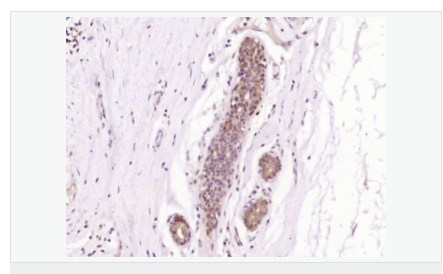

| 產(chǎn)品應(yīng)用 | WB=1:500-2000 ELISA=1:5000-10000 IHC-P=1:100-500 IHC-F=1:100-500 ICC=1:100-500 IF=1:100-500 (石蠟切片需做抗原修復(fù)) not yet tested in other applications. optimal dilutions/concentrations should be determined by the end user. |

| 細胞定位 | 細胞漿 細胞膜 |